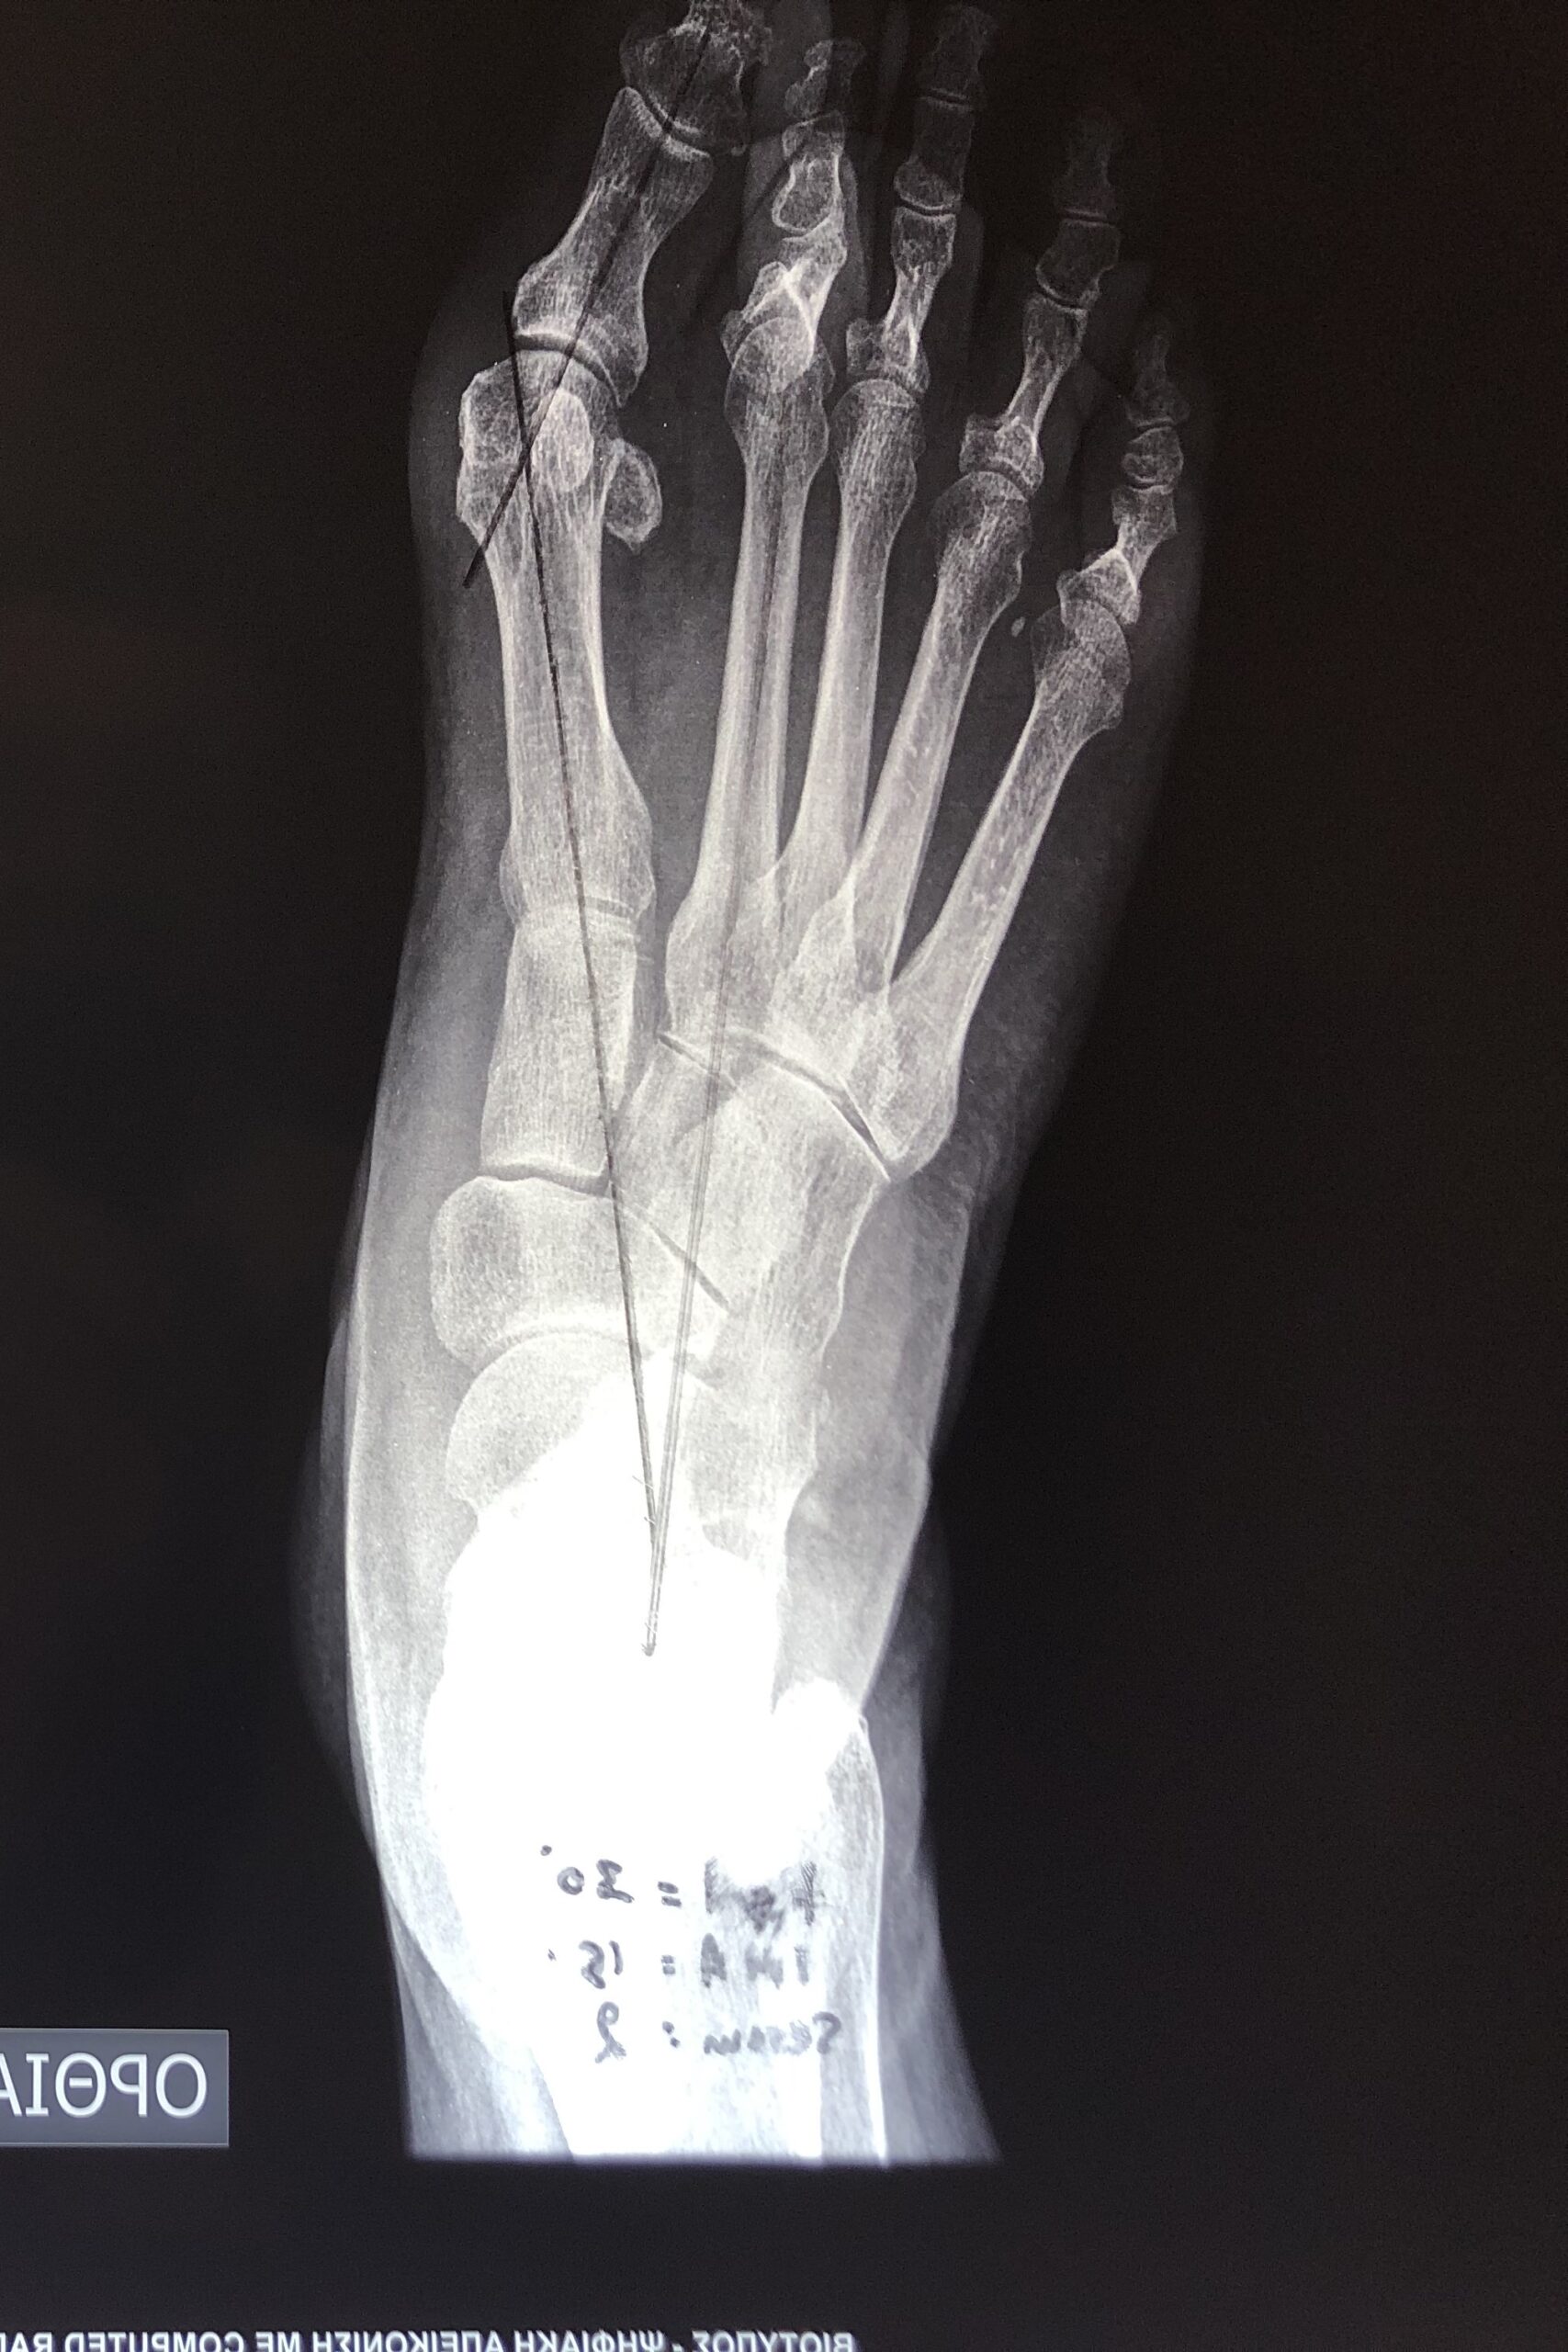

Η διάγνωση της πάθησης πραγματοποιείται εύκολα, καθώς η παραμόρφωση είναι εμφανής ακόμη και στα αρχικά στάδια της πάθησης. Ο θεράπων ορθοπαιδικός προχωρά αρχικά σε μια λεπτομερή λήψη του ατομικού ιστορικού του ασθενούς και στην κλινική εξέτασή του. Παρόλο που η διάγνωση πραγματοποιείται εύκολα μέσω αυτής, ο ακτινολογικός έλεγχος είναι απαραίτητος, για τη σταδιοποίηση της πάθησης (μέτρηση γωνίας βλαισότητας μεγάλου δακτύλου, διαμετατάρσιας γωνίας, γωνίας περιφερικής άρθρωσης μεταταρσίου, κλπ.) Ο καθορισμός του σταδίου είναι βαρύνουσας σημασίας για την επιλογή της κατάλληλης θεραπείας για τον κάθε ασθενή.

Έχουν περιγραφεί στην διεθνή βιβλιογραφία πάνω από 130 διαφορετικές χειρουργικές τεχνικές για την διόρθωση του βλαισού μεγάλου δακτύλου. Περιλαμβάνουν επεμβάσεις στα μαλακά μόρια της άρθρωσης (θύλακος, σύνδεσμοι, τένοντες) και στα οστά με διενέργεια διορθωτικών οστεοτομιών (σε διαφορα επίπεδα του πρώτου μεταταρσίου και της εγγύς φάλαγγας του μεγάλου δακτύλου). Η χρήση της πιο κατάλληλης τεχνικής και ο συνδυασμός αυτών καθορίζεται από τον βαθμό της παραμόρφωσης, από την ακτινολογικά της χαρακτηριστικά, αλλά και από τις δραστηριότητες του ασθενούς.

Επεμβάσεις ελάχιστης επεμβατικότητας, όπως είναι για παράδειγμα η διαδερμική τεχνική, μπορεί να χρησιμοποιηθεί για την αντιμετώπιση βλαισού μέγα δακτύλου στις πιο ήπιες παραμορφώσεις.